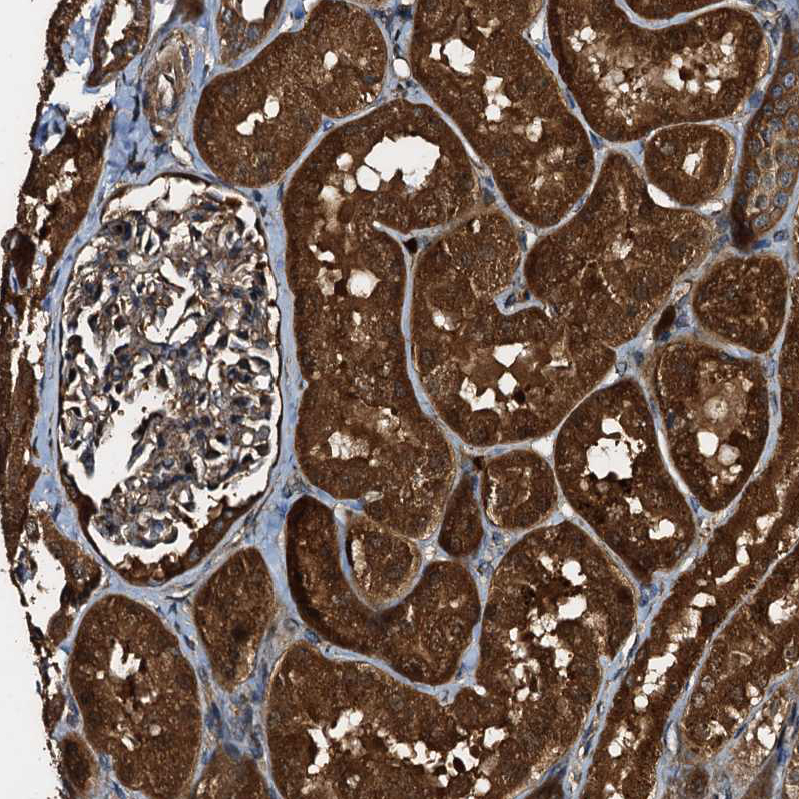

Immunohistochemical staining of human cerebral cortex, colon, lymph node and testis using Anti-PEX5 antibody HPA039259 (A) shows similar protein distribution across tissues to independent antibody HPA039260 (B).